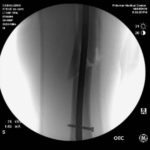

Vor ein paar Stunden wurde Steve deswegen im Palomar Medical Center Escondido operiert. Wie er selber berichtet, ist bei der OP an seinem Spiralbruch, linker Oberschenkel, alles perfekt abgelaufen.

An den Fotos unten kann man gut erkennen, dass der Knochen nun durch ein Titanstück und zwei Schrauben zusammengehalten wird. Den Moment des Sturzes hat Caballero auf Instagram hochgeladen. Den Clip findet ihr unter den Fotos.